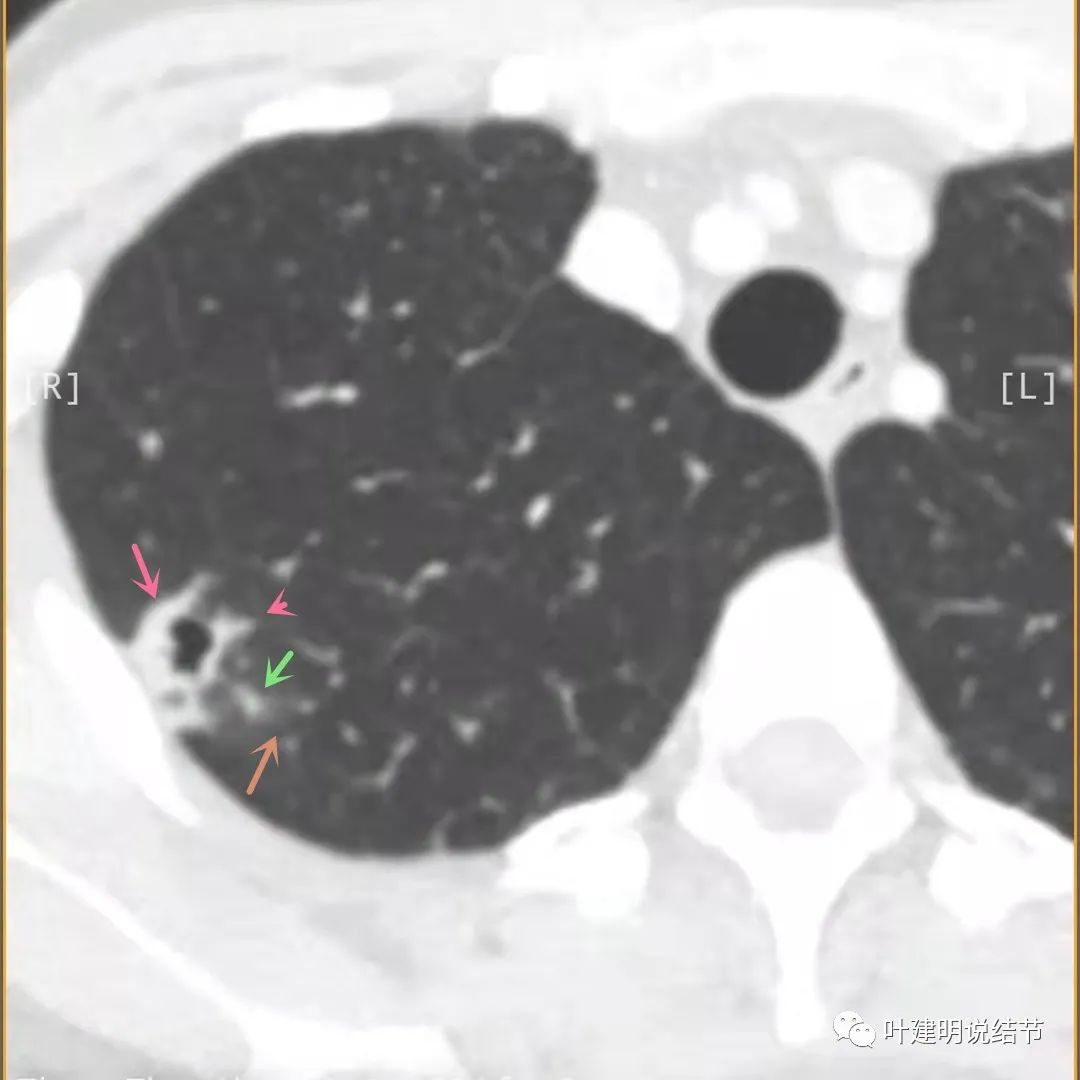

主病灶边界较清(红色箭头),实性部分密度过高(粉色箭头),病灶边缘向内凹,缺乏膨胀性(桔色箭头),病灶有空腔(黄色箭头)

邻近胸膜有增厚(蓝色箭头),主病灶的壁密度过高且整个壁密度都高(粉色箭头),旁边有磨玻璃影,散且模糊(砖色箭头)。内壁不均质(此不舒服)

邻近胸膜有增厚(蓝色箭头),主病灶囊壁密度过高(粉色箭头),内部有突起(细红色箭头),旁边有磨玻璃影,散且模糊(砖色箭头),中间有空腔,内壁有些区域又是光滑的

邻近有卫星灶(绿色箭头),主病灶密度过高(粉色箭头),旁边有磨玻璃影,散且模糊(砖色箭头)

邻近胸膜有增厚(蓝色箭头),主病灶边缘较为平直,缺乏膨胀性(桔色箭头),实性部分密度过高(粉色箭头),旁边有磨玻璃影,散且模糊(砖色箭头)